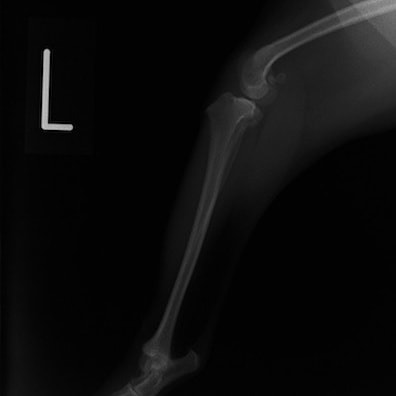

■ 症例22 ポメラニアン 1歳5か月 去勢雄

左後肢の挙上を主訴に来院した。整形学的検査、レントゲン検査より左右の膝蓋骨脱臼(左GradeⅡ〜Ⅲ、右Grade Ⅱ)を認めた。また、脛骨の前方引き出し試験の際に、引き出し兆候は認められないものの、疼痛が認められたため、前十字靭帯の損傷が疑われた。術中における、目視および関節内の操作によって、前十字靭帯の損傷や過伸展といった異常が認められなかったため、膝蓋骨脱臼の整復のみ実施した。手術手技は縫工筋及び内側広筋の解放、脛骨粗面の外側転位、滑車ブロック形造溝術、内外側関節包の縫縮を実施した。本症例は跛行もなく経過良好である。しかし、頸骨高平部の角度(TPA)が 右26.2°、左24.9°であり、解剖学的に前十字靭帯損傷のリスクが高いことから今後の経過に注意が必要である。